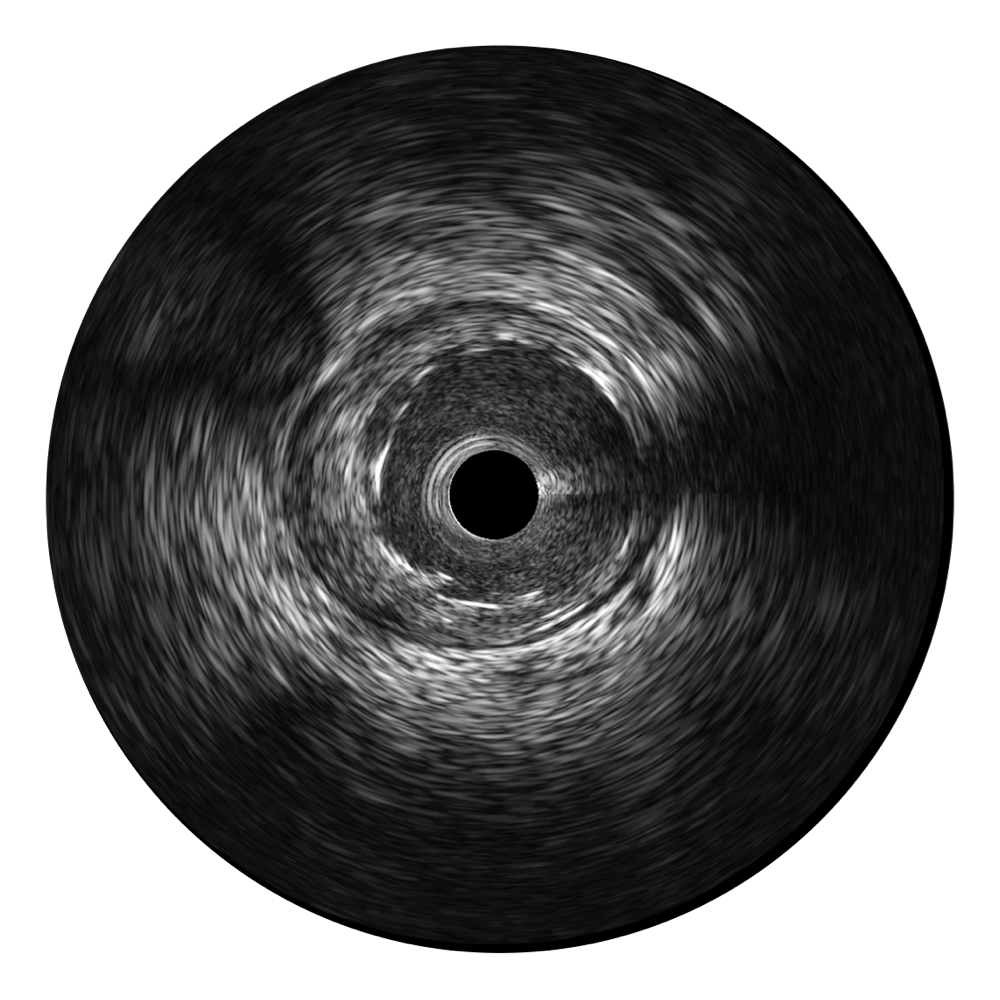

美狮贵宾会官网宽频IVUS图像

传统IVUS图像

对比传统IVUS导管成像,美狮贵宾会官网宽频IVUS图像的近场支架梁显影更细腻,远场中膜外血管仍清晰可辨,兼顾远中近,兼顾分辨力与穿透深度